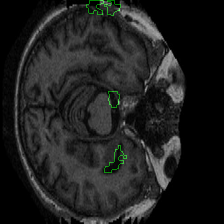

Figure 1 presents attribution maps generated using PWIG for a selection of MRI scans across all four diagnostic categories. The highlighted regions (in green) correspond to the areas that contributed most significantly to the model’s decision. Notably, we observe consistent emphasis on anatomical structures that align with clinical markers of dementia, including cortical and subcortical regions. For instance, in the moderate and mild dementia examples, the model focuses on regions exhibiting visible atrophy or abnormal morphology. In contrast, attribution maps for non-demented subjects appear more diffuse and less concentrated, reflecting the model’s detection of normal anatomical patterns.

The results in Figure 1 demonstrate that PWIG can effectively produce interpretable and clinically meaningful explanations for model predictions in medical imaging tasks.

Figure 1: PWIG attribution maps across dementia categories using the OASIS-1 dataset. Green overlays indicate regions with the highest attribution scores.